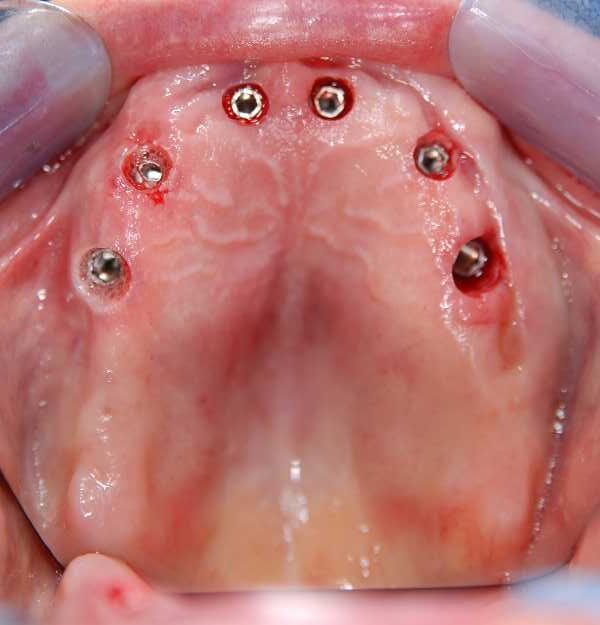

Patient 6 All-on-8 Maxilla - Gallery

Pic 3 Aerial view of Maxilla 2months post-extraction